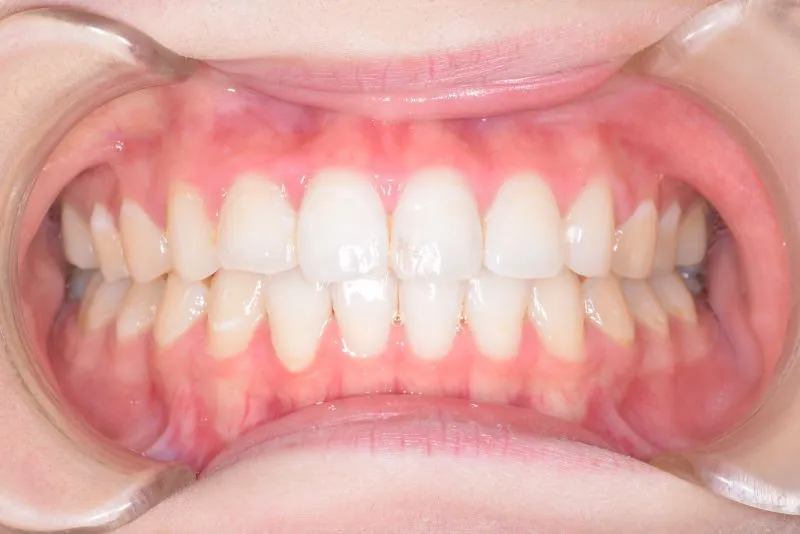

治療経過1

再治療の時は、上の歯は前から見えにくいオリジナル固定装置、下の歯はマルチブラケット装置を使用し、治療しました。

治療回数62回、1年6ヶ月の治療期間で矯正治療を終了しました。

前回の治療で歯の根っこの部分の位置を治していたので、全部前から付けるのではなく最低限見える装置で治せました。

一度治療して、後戻りでお困りの場合のご相談もお待ちしております。